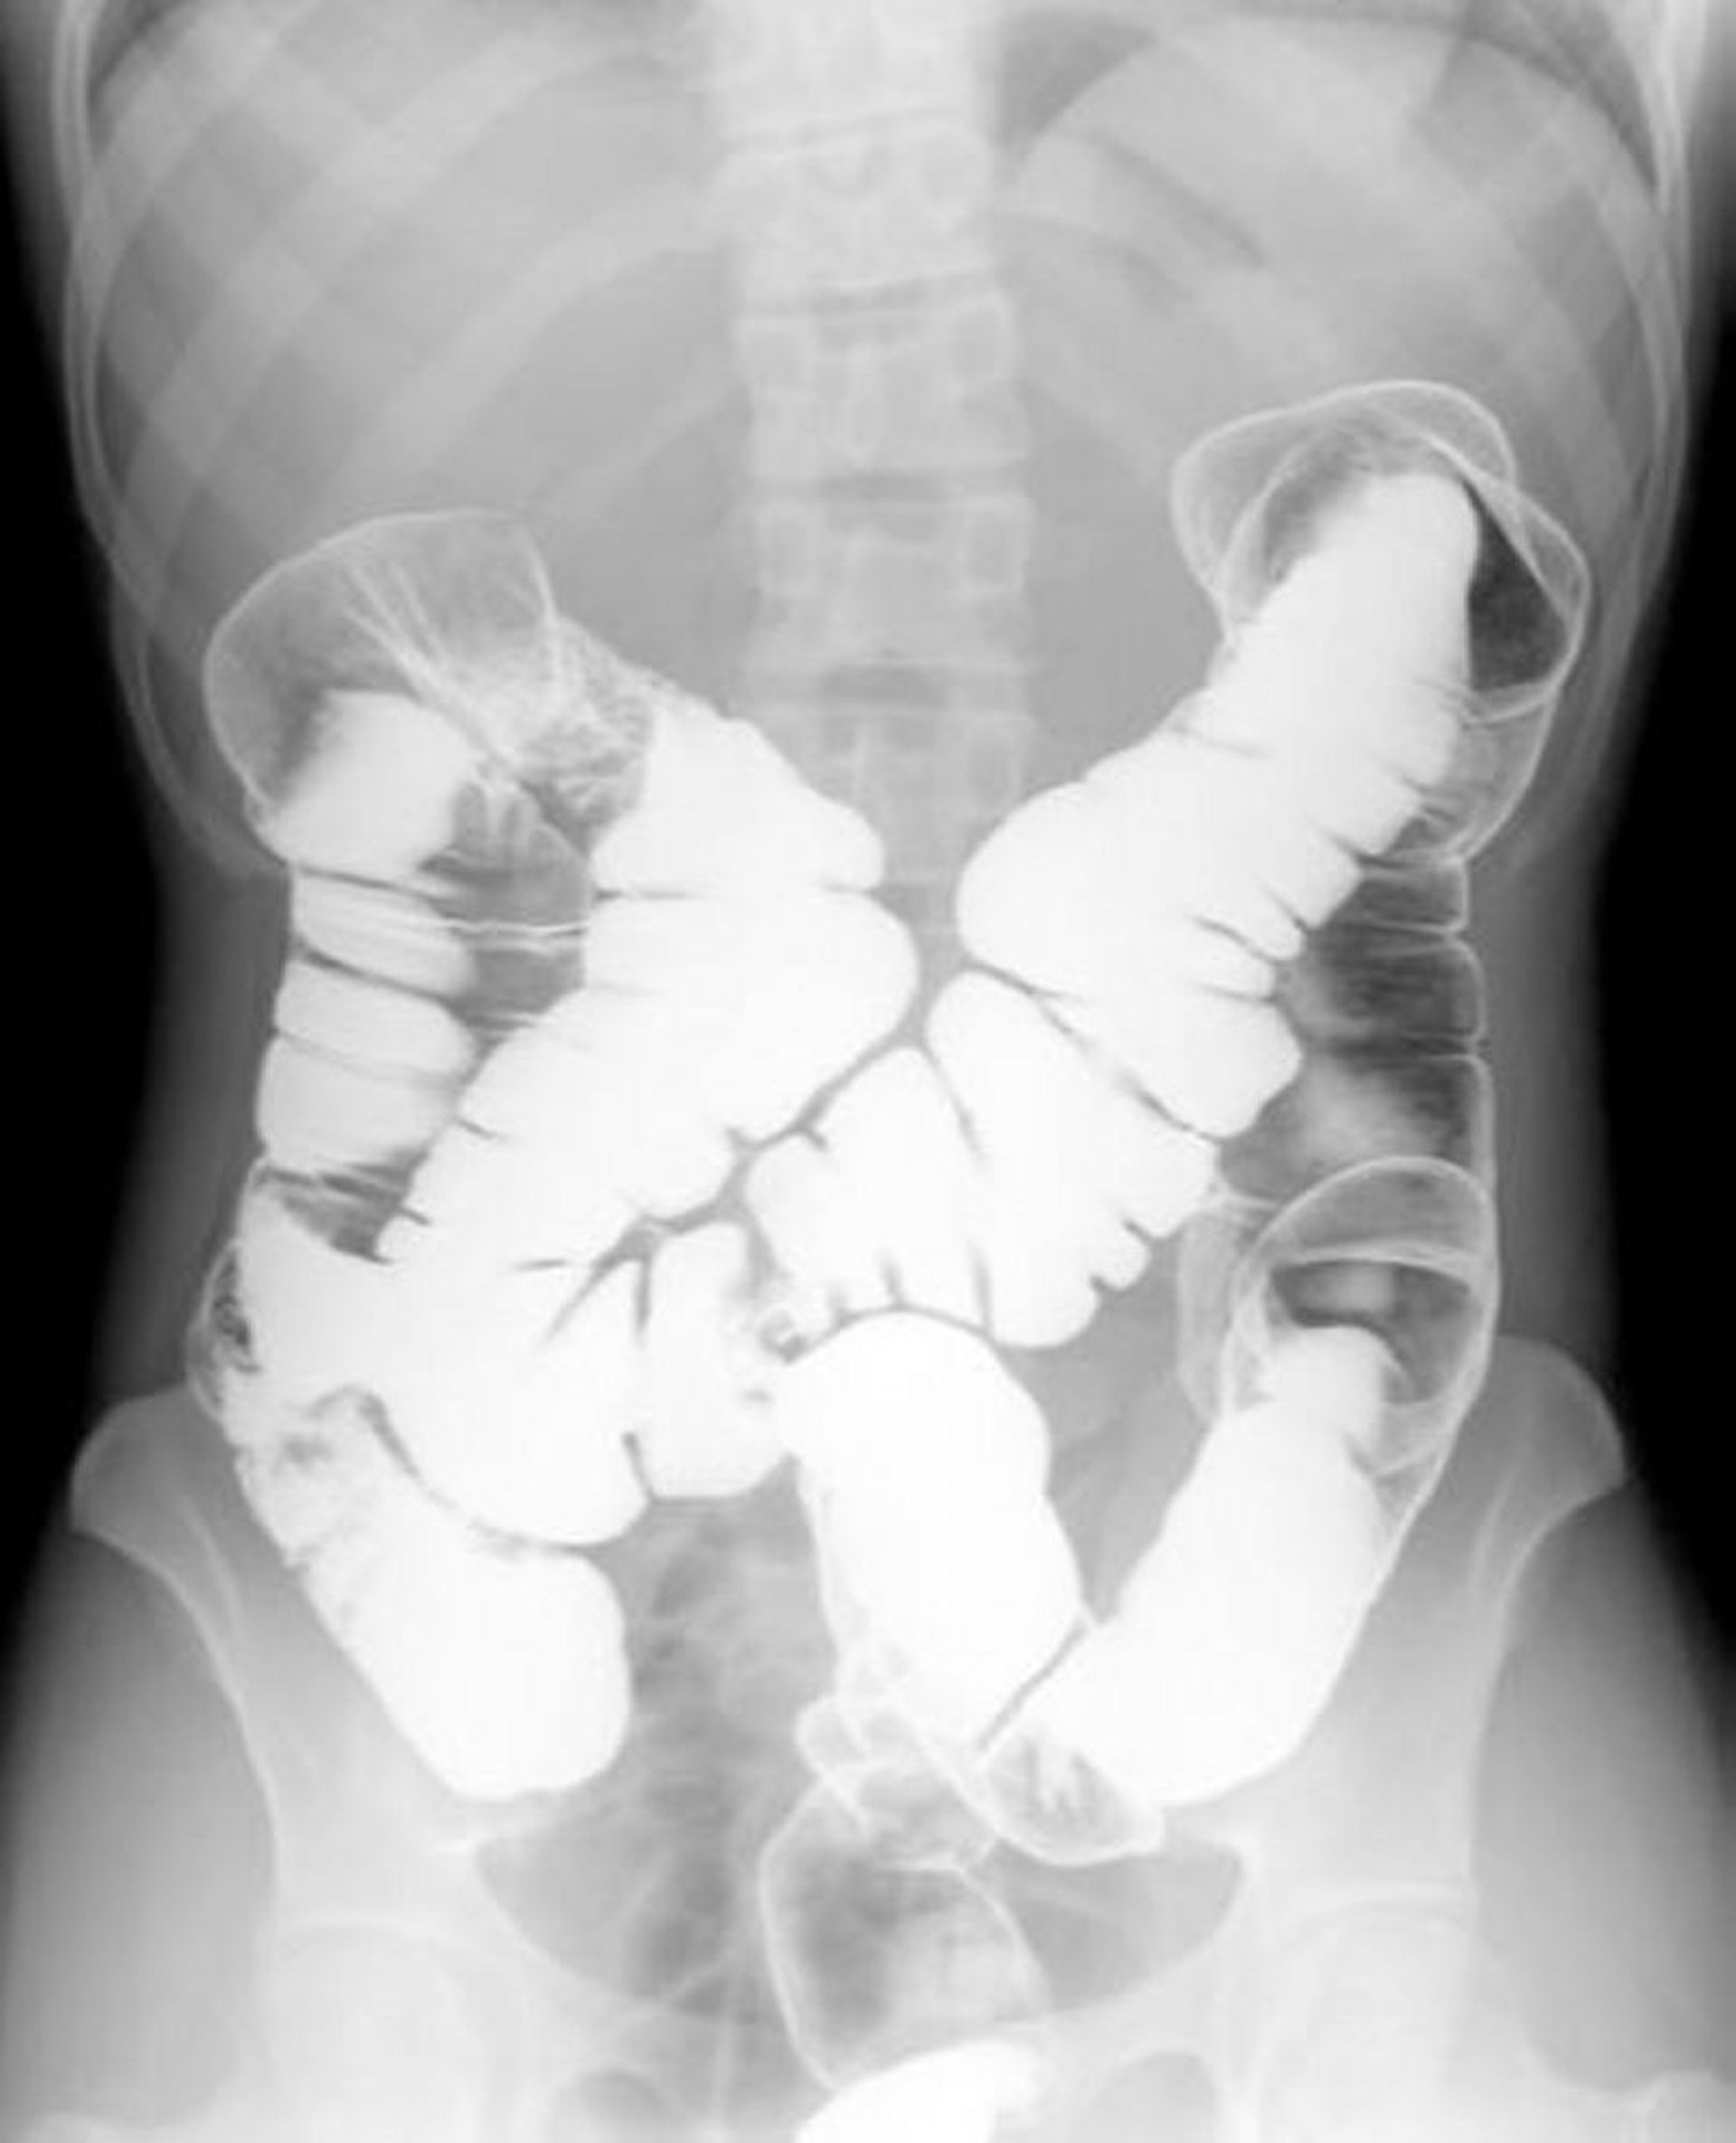

Ирригоскопия с двойным контрастированием: нормальная анатомия

На этом изображении показано распределение воздуха и бариевой взвеси по стенкам нормального толстого кишечника.